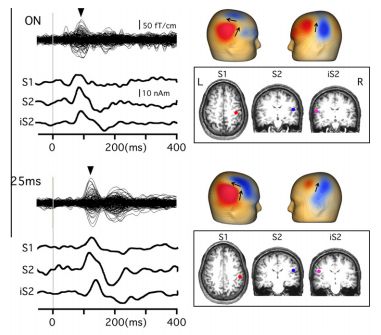

Saito K, Onishi H, Miyaguchi S, Kotan S, Fujimoto S. Effect of paired-pulse electrical stimulation on the activity of cortical circuits. Frontiers in Human Neuroscience. 2015; 9: 671. doi:10.3389/fnhum.2015. 00671.

Sugawara K, Onishi H, Yamashiro K, Kojima S, Miyaguchi S, Kirimoto H, Tsubaki A, Tamaki H, Shirozu H, Kameyama S. The effect of anodal transcranial direct current stimulation over the primary motor or somatosensory cortices on somatosensory evoked magnetic fields.Clin Neurophysiol. 2014 (in press)

Onishi H, Sugawara K, Yamashiro K, Sato D, Suzuki M, Kirimoto H, Tamaki H, Murakami H, Kameyama S. Effect of the number of pins and inter-pin distance on somatosensory evoked magnetic fields following mechanical tactile stimulation. Brain Research, 2013, 1535:78-88